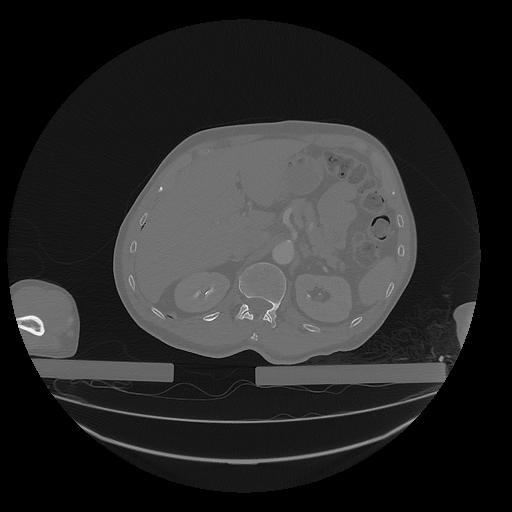

31 PULMON,CE,Vol,1.0,PULMON,,